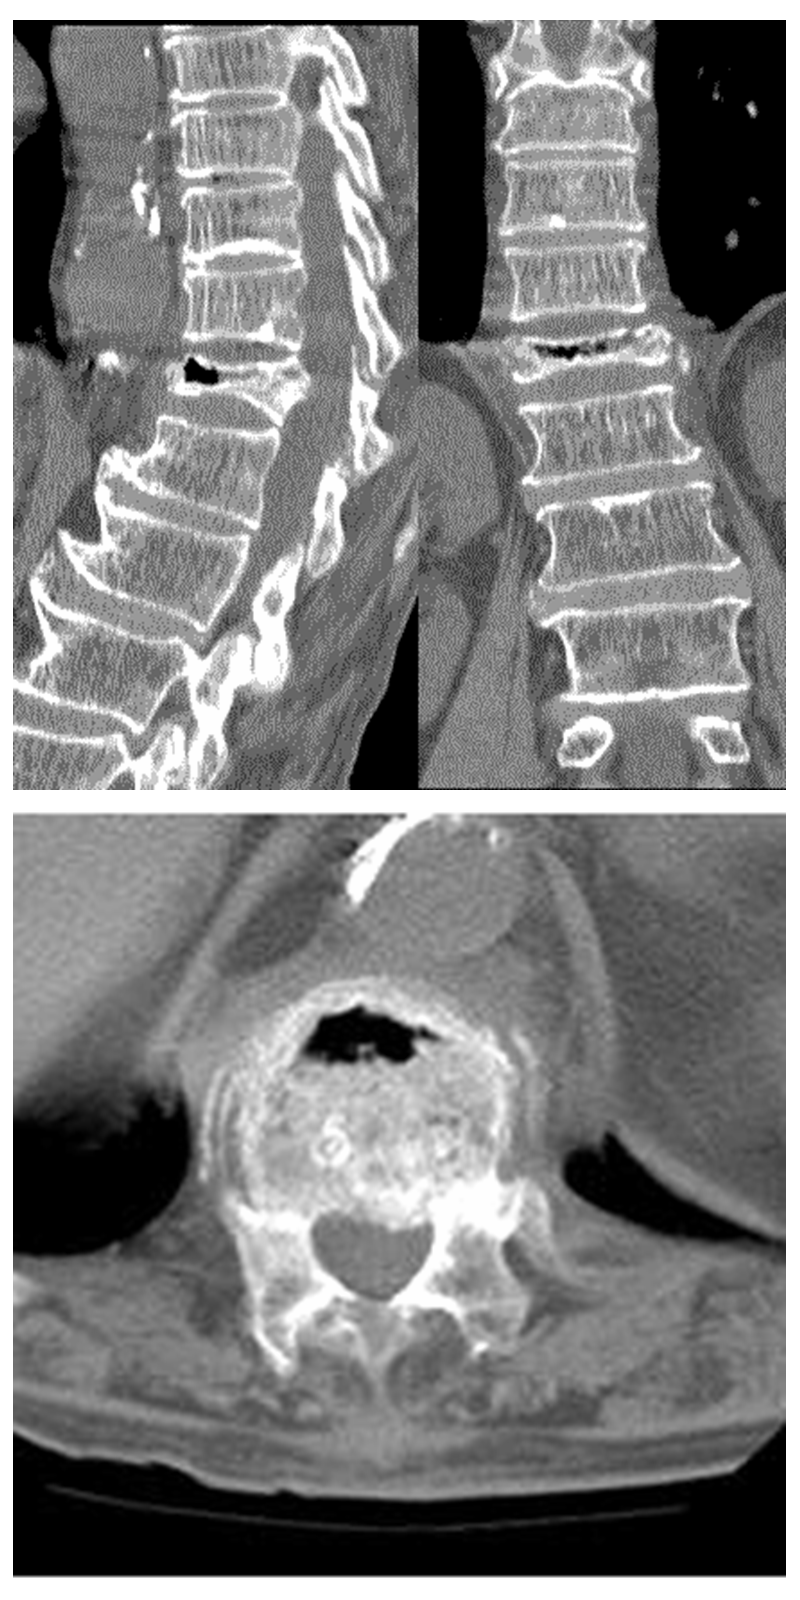

③在CT片上:矢状位和冠状位可见椎体内存在裂缝。与Xray片相比,裂隙更加不均匀、不规则;其诊断率较X平片更高;

④在核磁上:诊断率最高,IVC主要有两种表现:当裂隙内主要是液体时,在T1上低信号,T2上高信号。(见上图)

当裂隙内是气体时,T1和T2相上均为低信号(见上图)。